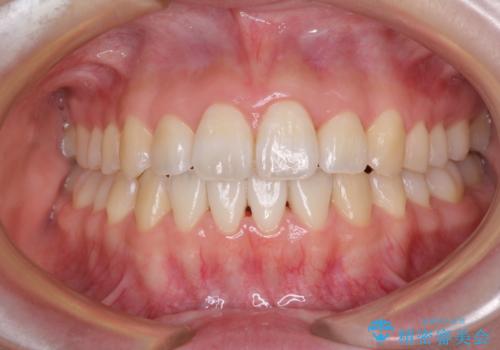

- 学生時代に行った抜歯矯正の後戻りで、隙間ができてしまったことを気にして来院された患者様です。

マウスピース矯正を検討されていましたが、後戻りの隙間が非常に大きく、奥歯を前方に移動させる必要があるため、ワイヤー装置にて矯正治療を行うこととしました。

舌の突出癖が非常に強く、その影響で隙間ができてしまったので、舌のトレーニングをしっかりと行っていただきました。

上顎歯列は歯の移動量が少なかったため、セラミッククラウンは装置を装着せずに治療を終えることができました。